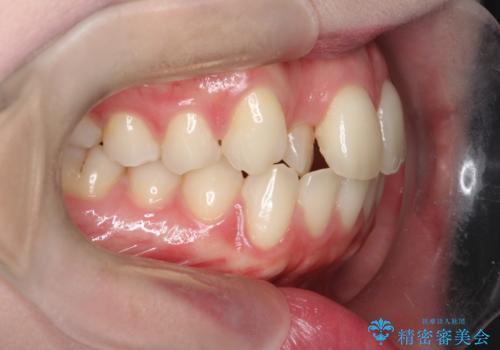

上下4本の抜歯と審美ワイヤー矯正で整った歯並びへ

- 患者様は、歯並びの乱れを整えたいとのことで来院されました。診察の結果、歯列のスペース不足が原因で前歯のガタつきが目立ち、噛み合わせにも影響が出ている状態でした。歯を正しく並べるためにはスペースの確保が必要と判断し、上下の小臼歯4本を抜歯して、審美ワイヤー矯正(白いワイヤーと透明ブラケット)で治療を行う計画を立てました。

まず、抜歯によって歯を動かすためのスペースを確保。その後、審美ワイヤー矯正を用いて、前歯のガタつきを整えながら、噛み合わせの調整も行いました。審美装置を使用することで、矯正中も目立ちにくく、自然な仕上がりを目指して治療を進めました。治療の結果、歯並びがきれいに整い、口元のバランスも改善しました。患者様からは「歯並びがきれいになり、自信を持って笑えるようになった」と喜びの声をいただきました。